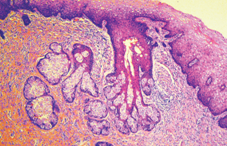

Mucinous cells with blue cytoplasm and flattened nuclei, intermixed with squamous cells containing dense eosinophilic cytoplasm and round nuclei. Courtesy Dr. V. Penopoulos.